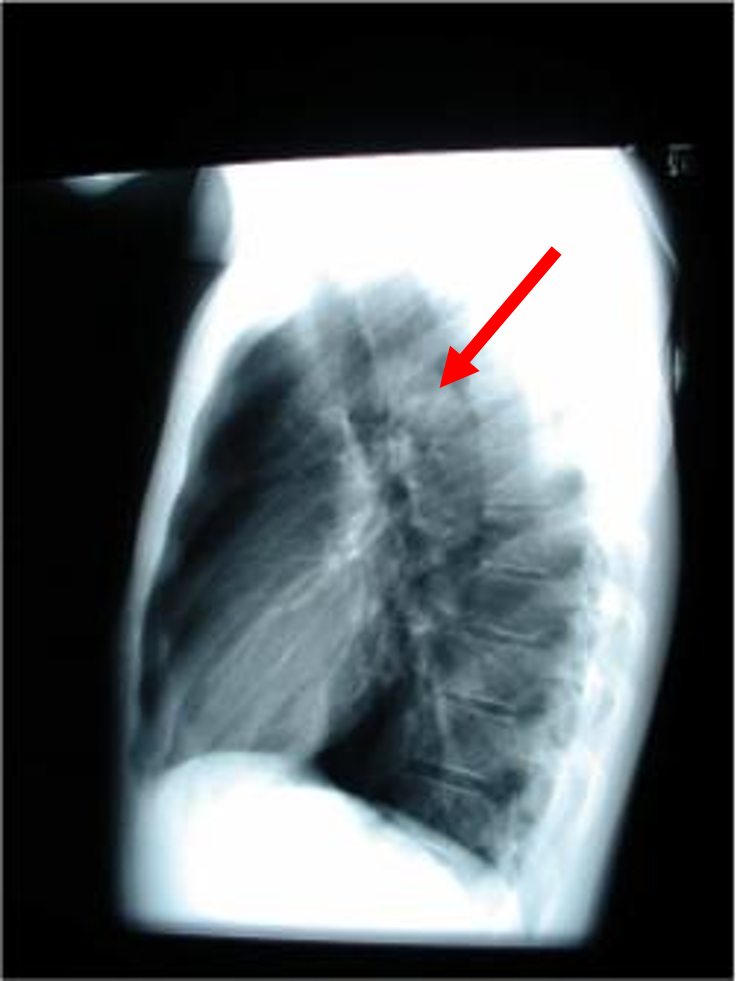

what view is this?

three indentifiers

lateral chest